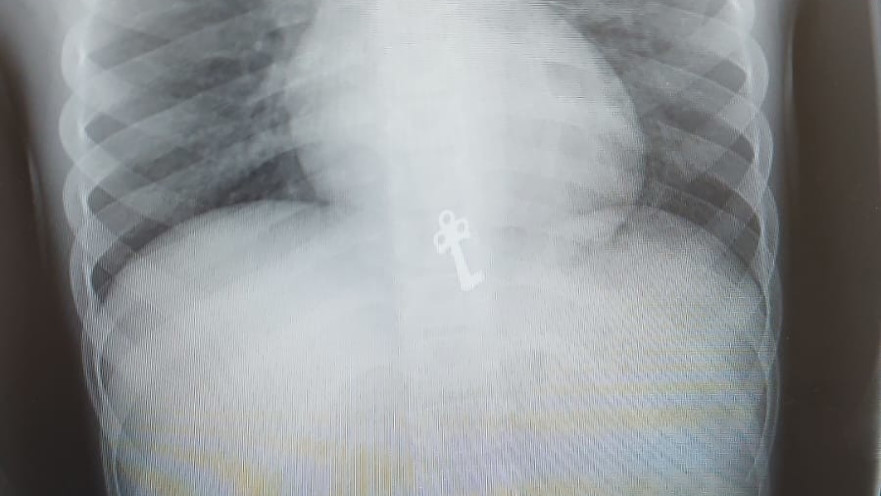

הצילום שנערך לילד, טרם הטיפול הפולשני

הצילום שנערך לילד, טרם הטיפול הפולשני | צילום: דוברות מרכז פרנקל לרפואה דחופה

ילד בן שבע, תושב ירושלים, הועבר לחדר המיון "מרכז פרנקל לרפואה דחופה" ביד שרה, לאחר שבלע את מפתח יומן הכיתה של אחותו הגדולה. בצילום שנערך לו במקום, מצא רופא הילדים ד"ר חגי שטרן את המפתח הזעיר כשהוא בקיבתו של הילד.

בעקבות כך שהמפתח משונן ודוקרני, הדבר חייב פעילות פלשנית של של הוצאת המפתח מחשש לסיכון ולקרע במעבר למעי, ובשל כך הועבר התינוק לחדר ניתוח בבית החולים.